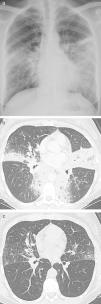

Presentación de los casosCaso 1Una mujer de 44 años no fumadora acudió con tos y disnea. La exploración física fue normal y no presentaba fiebre. En su analítica destacó una PCR elevada (122mg/l). En las pruebas de función pulmonar se determinó una espirometría normal (FEV1 94% y FVC 96% del valor predicho), volúmenes pulmonares normales (TLC 102% y FRC 119% del valor predicho) y DLCO disminuida (68% del valor teórico). Las pruebas de imagen torácica revelaron enfermedad bilateral del espacio aéreo y nódulos peribroncovasculares (fig. 1 a y b). La biopsia con aguja gruesa mostró intersticio pulmonar engrosado, infiltrado linfoplasmocitario denso, vasos sanguíneos fibróticos y de 30 a 40 células plasmáticas IgG4+ por campo de gran aumento. El nivel de IgG4 en suero era de 573mg/dl (rango normal: 3-201mg/dl). En la visita de seguimiento (18 meses desde el diagnóstico), los síntomas pulmonares se habían resuelto espontáneamente y los hallazgos radiológicos habían experimentado un retroceso parcial (fig. 1c). Los resultados de la espirometría, los volúmenes pulmonares y la DLCO no cambiaron. Varios meses después del alta, se diagnosticó dacrioadenitis al referir la paciente problemas de ojo seco.